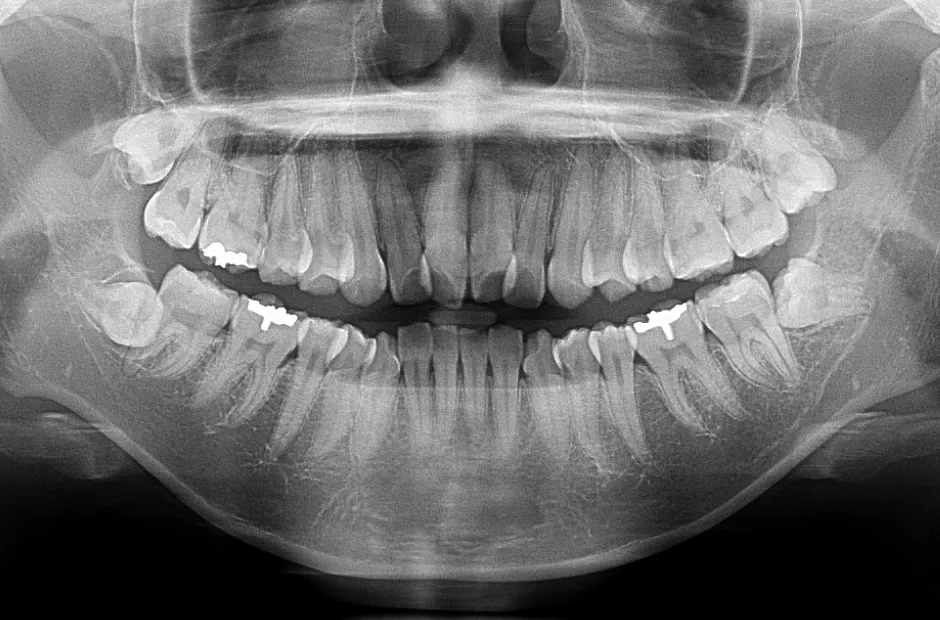

叢生

| 診断名・主訴 | 叢生 |

|---|---|

| 年齢・性別 | 43歳・女性 |

| 治療期間・回数 | 2年7か月 27回 |

| 治療に用いた主な装置 | 舌側矯正 |

| 抜歯部位 | 両顎4,4 |

| 治療費 | 100万円(税抜) |

| リスク・副作用 | 装置による違和感・疼痛・歯肉退縮・歯根吸収・虫歯のリスクなど |

治療前